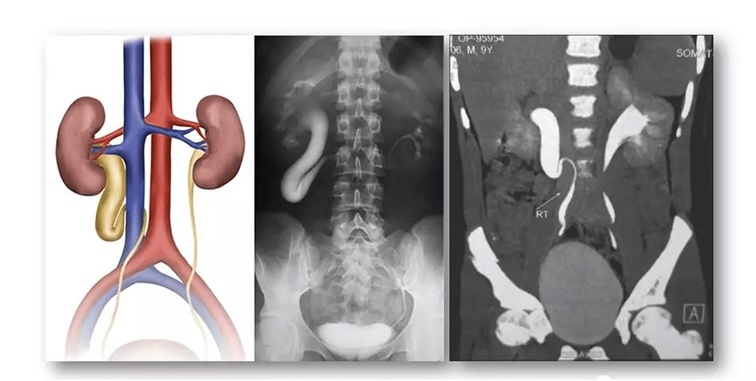

下腔静脉后输尿管临床上少见,发病率为0.13%,男性患者较多,临床上男女比例约为2.8:1,常见于右侧,内脏转位及重复腔静脉时可见于左侧。腔静脉后输尿管由HOCHSTETTER于1893年在尸检中首次描述,1940年首次临床诊断。BATESON等将腔静脉后输尿管分为Ⅰ型(低襻型)和Ⅱ型(高襻型)2型。Ⅰ型(低襻型)常见,占90%左右,输尿管于L3~4水平呈鱼钩状或“S”状穿入下腔静脉后方,在下腔静脉与腹主动脉之间穿出。下腔静脉与脊柱间隙小,易产生梗阻症状。Ⅱ型(高襻型)少见,肾盂输尿管移行处或部分肾盂横行向左于L2-3水平至下腔静脉后方,同样在下腔静脉与腹主动脉之间穿出,因下腔静脉与脊柱间有右肾动脉,二者有一定的间隙,且肾盂部分较宽,故梗阻多数较轻,不需手术治疗。有报道腔静脉后输尿管可并发蹄铁形肾、对侧肾畸形如肾发育不良、异位、积水、旋转不良,先天性输精管缺失、尿道下裂、多囊肾、腹膜后纤维化及隐睾等。

(1)IVU是诊断腔静脉后输尿管的主要方法,影像表现为肾积水、输尿管上段扩张向中线移位,典型者呈现S形或“鱼钩状”影像。逆行尿路造影可全程显示输尿管,缺点为有创检查。右侧位片可见脊柱与扩张的输尿管重叠,而中段输尿管恢复在脊柱前方的正常位置,此点为重要征象。